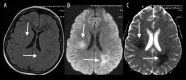

Toxic leukoencephalopathy results from damage to the white matter caused by various toxins. It manifests itself as white matter signal abnormalities with or without the presence of restricted diffusion. These changes are often reversible if the insulting agent is removed early, with the exception of posthypoxic leukoencephalopathy that can manifest itself 1-2 weeks after the initial insult. However, many other potential causes of white matter signal abnormalities can mimic the changes of toxic leukoencephalopathy. Thus, familiarity with the causes, clinical presentation and particularly imaging findings of toxic leukoencephalopathy is critical for early treatment and improved prognosis. The purpose of this pictorial essay is to familiarize the reader with the various causes of toxic leukoencephalopathy along with its differential diagnoses and mimics.